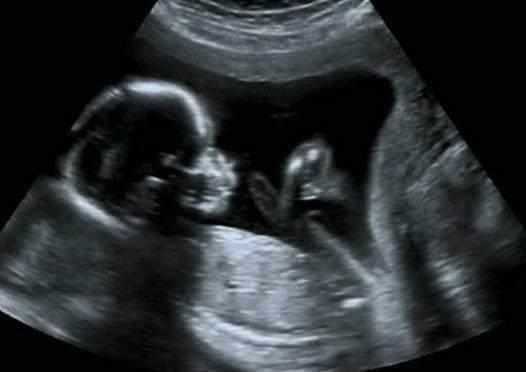

胎停育是指妊娠早期时胚胎因某些原因而导致发育停止。一般B超检查会发现妊娠囊内胎芽或胎儿形态不整,无胎心搏动或妊娠囊枯萎。有些孕妇的胎停育没有明显征兆,偶尔会感觉到腰酸腰痛、微量出血的症状,很多初为人母的孕妈妈没有这方面的经验,很容易忽视。

怀孕胎停什么症状,由于每个人的身体素质不一样,胎停育的症状也会有所差异,有些人可能没有任何反应,而突然出现小腹疼痛现象,如果出现长久的腰酸背痛以及微量出血的情况,为了稳妥起见,最好及时到医院做B超进行检查为好。流产(abortion)为妇科常见疾病,如处理不当或处理不及时,可能遗留生殖器官炎症,或因大出血而危害孕妇健康,甚至威胁生命;此外,流产易与妇科某些疾病混淆。妊娠于20周前终止,胎儿体重少于500克,称为流产(1966年世界卫生组织)。流产发生于孕12周前者,称为早期流产。发生于12周后者,称为晚期流产。